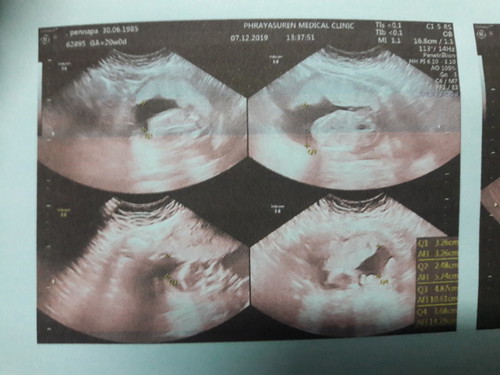

24week

ตั้งครรภ์ได้6เดือนแล้วค่ะ แม่ๆท่านไหนพอดูรุ้มั้ยค่ะว่า ช หรือ ญ ช่วยบอกที่ค่ะ??

ภาพไม่ชัดเลยแม่ มองไม่ออก